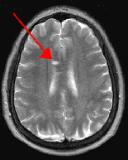

Fig. 4

Thin-section sagittal FLAIR images increase detection of small MS plaques even further, first reported by Hashemi, et al. (Ref. 1). They also have the advantage of clearly showing the corpus callosum and subependymal regions. An early sign of MS is subependymal nodularity and subcallosal striations (Ref. 1-2), not clearly visible on axial images. Fig. 3-4 in the same patient clearly show subcallosal MS plaques (arrows) along the undersurface of corpus callosum.